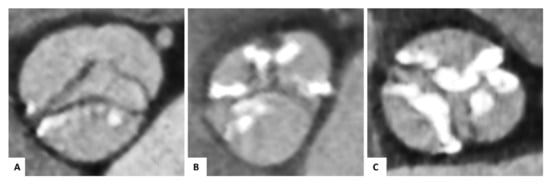

2.2. Morphology of the Bicuspid Aortic Valves

2.5. Image Analysis